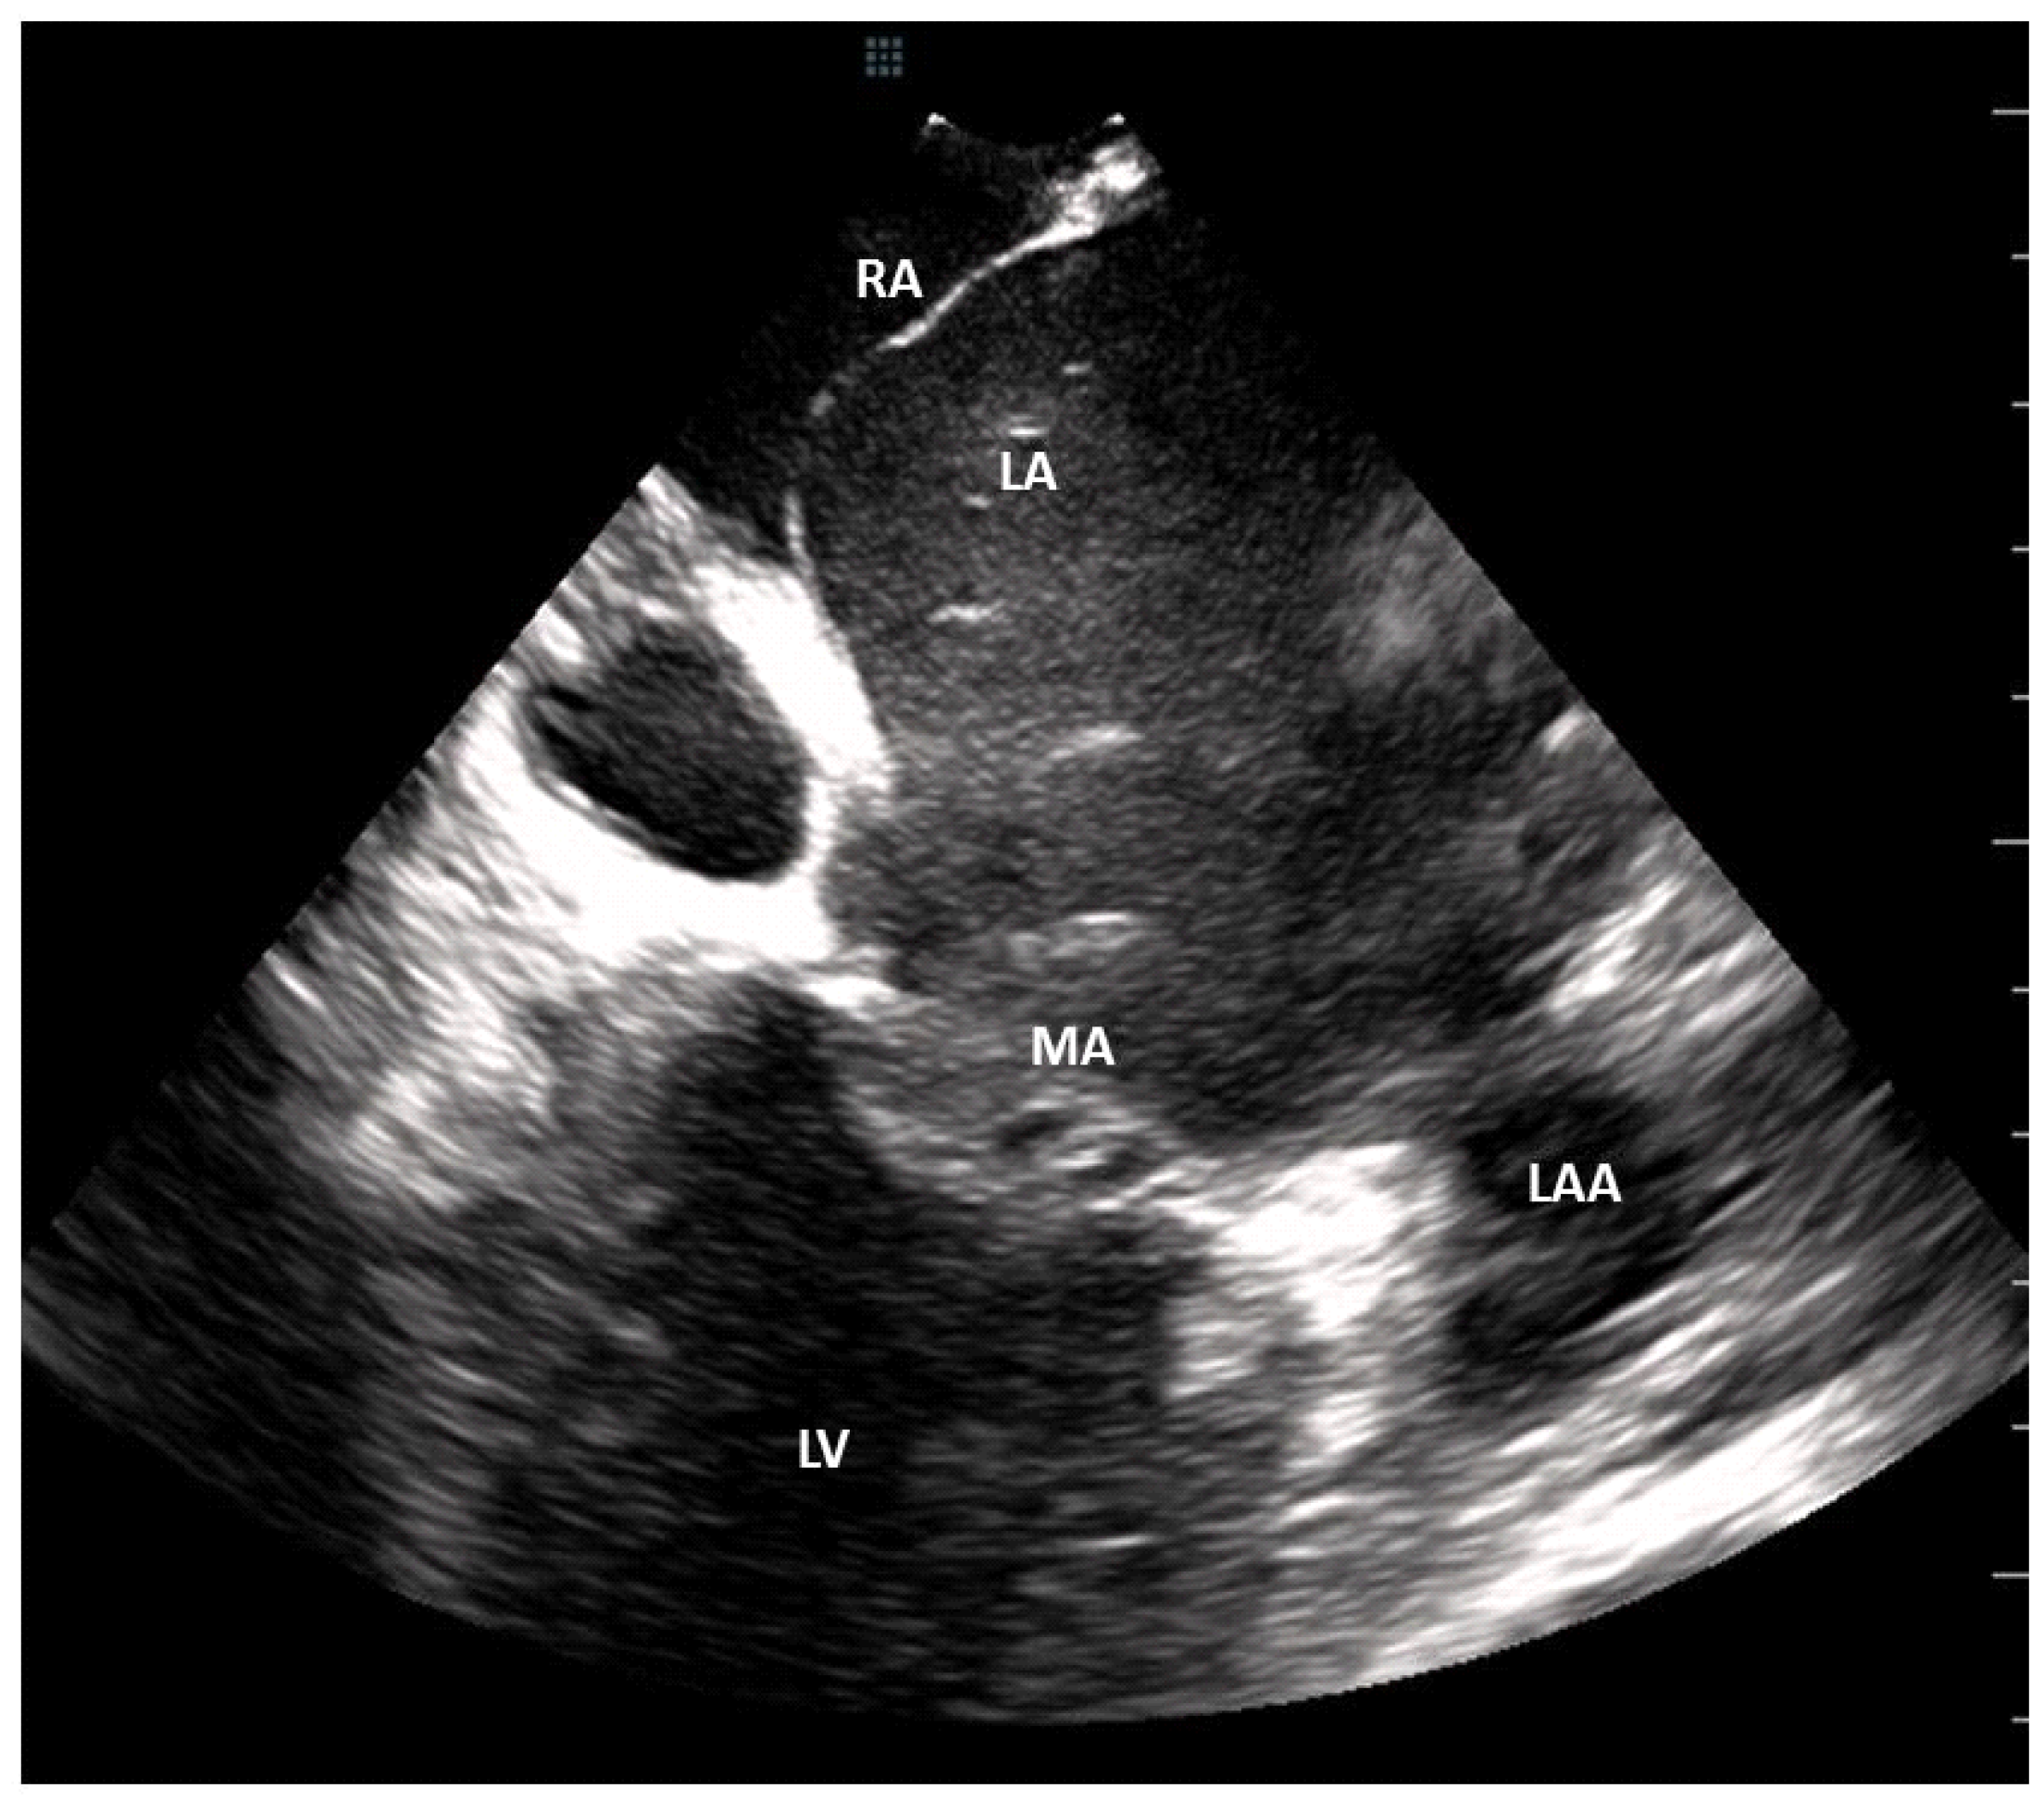

3.3. Thrombus Detection